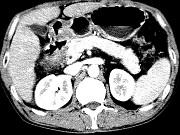

问题 女,63岁,右上腹疼痛,呈不规律性钝痛,伴恶心,时有呕吐,呕吐物为胃内容物混有胆汁,CT检查如图,最可能的诊断是()

选项 A.十二指肠克罗恩病 B.十二指肠结核 C.十二指肠癌 D.十二指肠淋巴瘤 E.十二指肠平滑肌瘤

答案 C